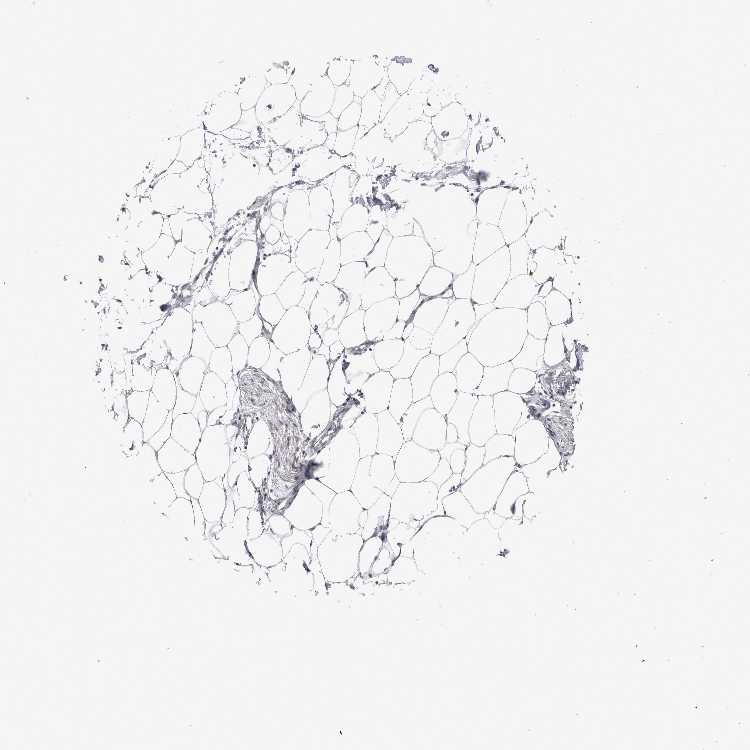

TISSUE PRIMARY DATA ADIPOSE TISSUE Show tissue menu

ADIPOSE TISSUE - Expression summary

ADIPOSE TISSUE - Antibody stainingi

Antibody staining in the annotated cell types in the current human tissue is reported as not detected, low, medium, or high, based on conventional immunohistochemistry profiling in selected tissues. This score is based on the combination of the staining intensity and fraction of stained cells.

Each image is clickable and will lead to virtual microscopy that enables deeper exploration of all samples and also displays staining intensity scores, fraction scores and subcellular localization as well as patient and tissue information for each sample.

Antibody HPA023323Antibody HPA028455

Adipocytes Not detectedNot detected